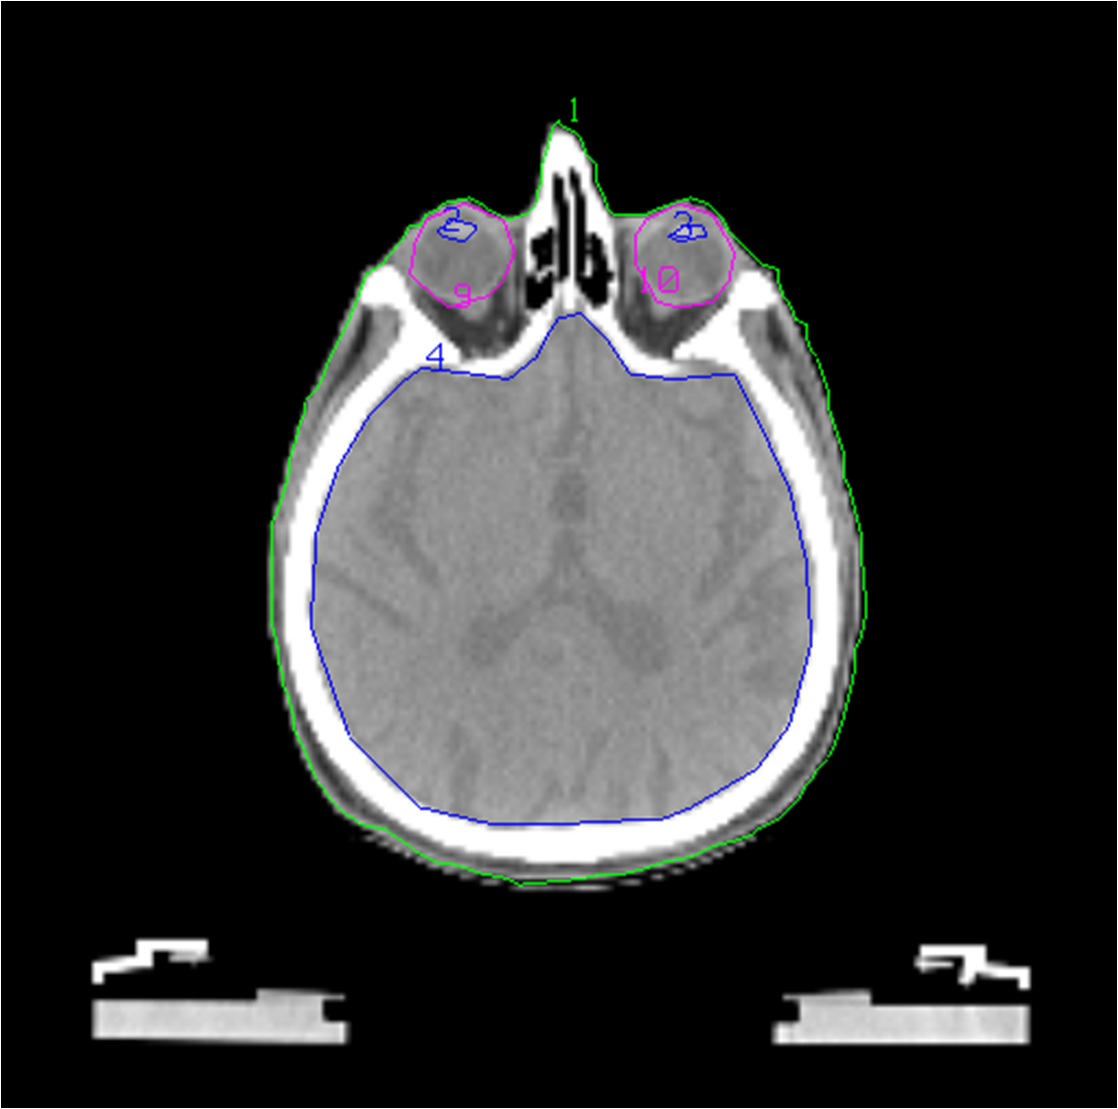

The whole process begins with patient positioning and body fixation and the creation of individualized 3D digital data sets of patient tumours and normal adjacent anatomy in CT. These data sets are then used to generate 3D computer images. Radiation oncologists make a contouring for tumour and organs of risks. Sometimes it is necessary to fusion the images, combining of MRI and PET-images into CT slices. The next steps are dose planning with a treatment planning system, acceptance of treatment plan and transporting of information into the treatment and simulating equipment through a computer network. After that the patient is placed on the simulator table and the final treatment position of the patient is verified using the fluoroscopic capabilities of the simulator. The images from simulator are compared with digitally reconstructed radiographs (DRRs) from treatment planning system. The clinical aspects of treatment simulation, be it with a conventional or CT simulator, rely on the positioning and immobilization of the patient as well as on the data acquisition and beam geometry determination. Treatment evaluation consists of verifying the treatment portals (through port films or on-line portal imaging methods) and comparing these with simulator radiographs or DRRs and/or performing in vivo dosimetry through the use of diodes, thermoluminescent dosimeters (TLDs) and other detectors.

Workflow in teletherapy:

• a. patient fixation using the different type of devices

• b. acquisition of CT data for treatment planning

• c. definition of the critical structures

• d. definition of the target volumes

• e. treatment planning (determination of field geometry and shielding, dose calculation)

• f. dosimetric control of the dose distribution for the treatment plan

• g. analyse the dose distribution a point of view to planning target volume and region of interest

• h. treatment simulation (conventional or CT-simulator)

• i. treatment verification with portal imaging or cone-beam CT.

Figure 13, 14, 15: Patient fixation

Figure: 16, 17: Contouring

Figure 18, 19: Treatment planning